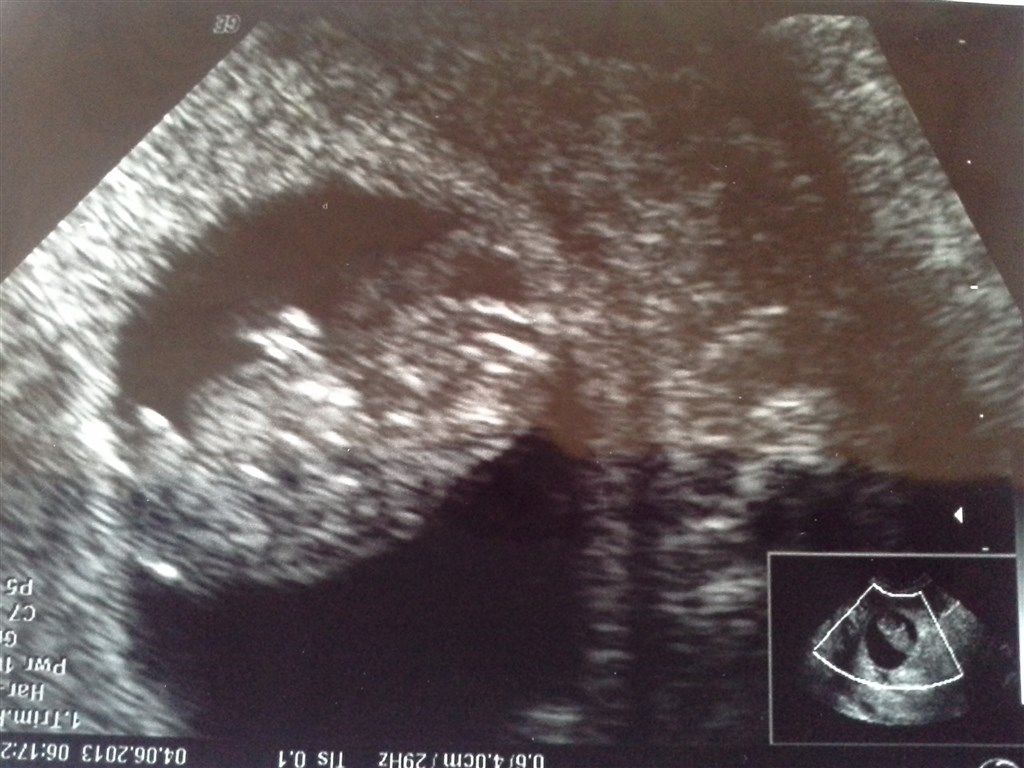

vores lille baby

Elling <3<3

Vedhæftede fotos (klik for at se i fuld størrelse)

Fin bæbs.. Hvor langt er du på billederne?

I følge skanningen 8+5

Vildt at man kan se så meget, det er jo ret tydeligt

Var også helt overrasket. Man kunne se den tog sine små hænder op til hovedet og alt muligt

Det var så stort